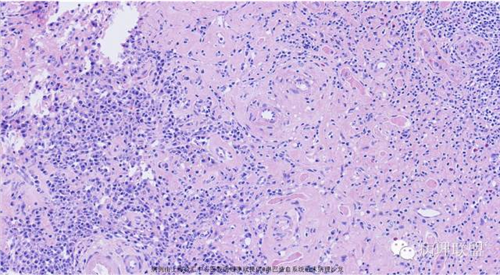

M,79岁,右半结肠粘膜下肿块。大小:6.5*6*6cm球形肿块,切面灰白质硬,界清。第一次取材。